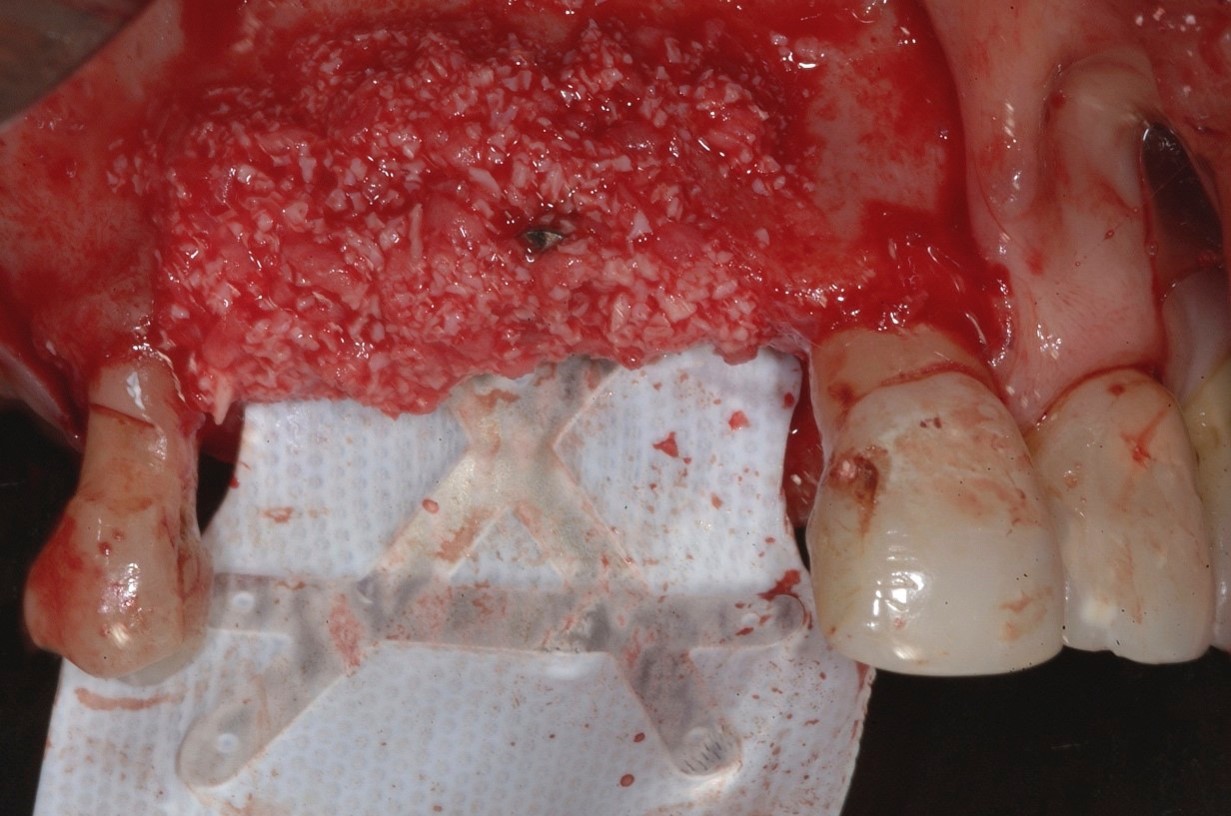

Fig 5. A dense e-PTFE membrane was adapted to the anatomical situation, and a graft composed of 30% deproteinized bone and 70% autogenous bone chips harvested from the mandibular retromolar area was placed.

Figure 5

Two dentine screws were placed to support the nonresorbable titanium-reinforced membrane both horizontally and vertically and to avoid collapse of the membrane itself toward the defect (Figure 4). A dense e-PTFE membrane was cut and folded to adapt it to the anatomical situation, and the graft was placed (Figure 5). The graft was a mixture of 30% deproteinized bone and 70% autogenous bone chips harvested from the mandibular retromolar area. The membrane was then adapted and fixed with free tacks in the buccal and palatal positions (Figure 6).